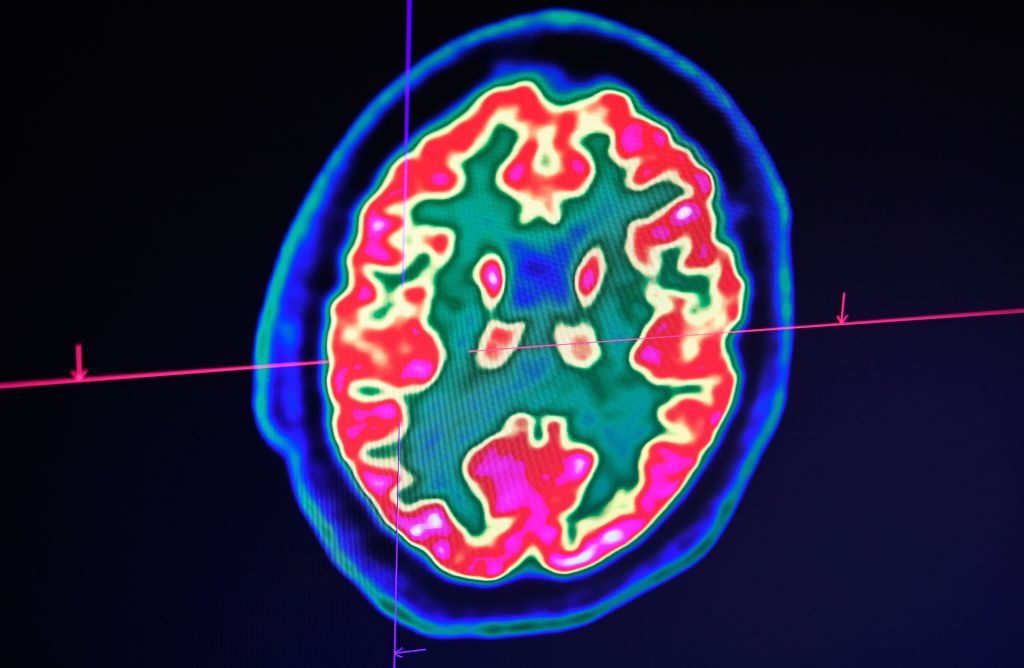

There Are Left-Brained And Right-Brained People

People like to claim that they are either left-brained or right-brained, meaning that they either rely on logic (left) or creativity (right). So, someone who is extremely good at math may be labeled as left-brained because they use their logic and analytics to deduce and solve problems.

Conversely, a painter is considered right-brained because of their artistic capabilities. It’s also said that it’s rare for people to use both and that you’re one or the other. This is false, as there’s no division between the talents of each hemisphere of your brain. In fact, they work together.